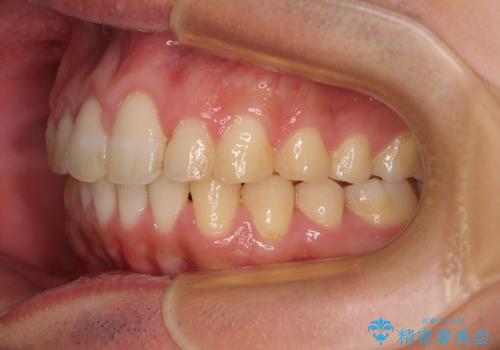

捻れて飛び出した前歯 インビザラインで整った前歯に

- 上下前歯のデコボコと、それに伴う出っ歯を気にして来院された患者様です。

インビザラインによる上下歯列の側方拡大と後方移動、IPR(歯と歯の間を削る)にるスペースの獲得により歯列を整えることとしました。

歯と歯の間を削ることでうまくスペースコントロールでき、また、毎日22時間以上しっかりとマウスピースを装着していただいたので、スムーズに治療が進みました。